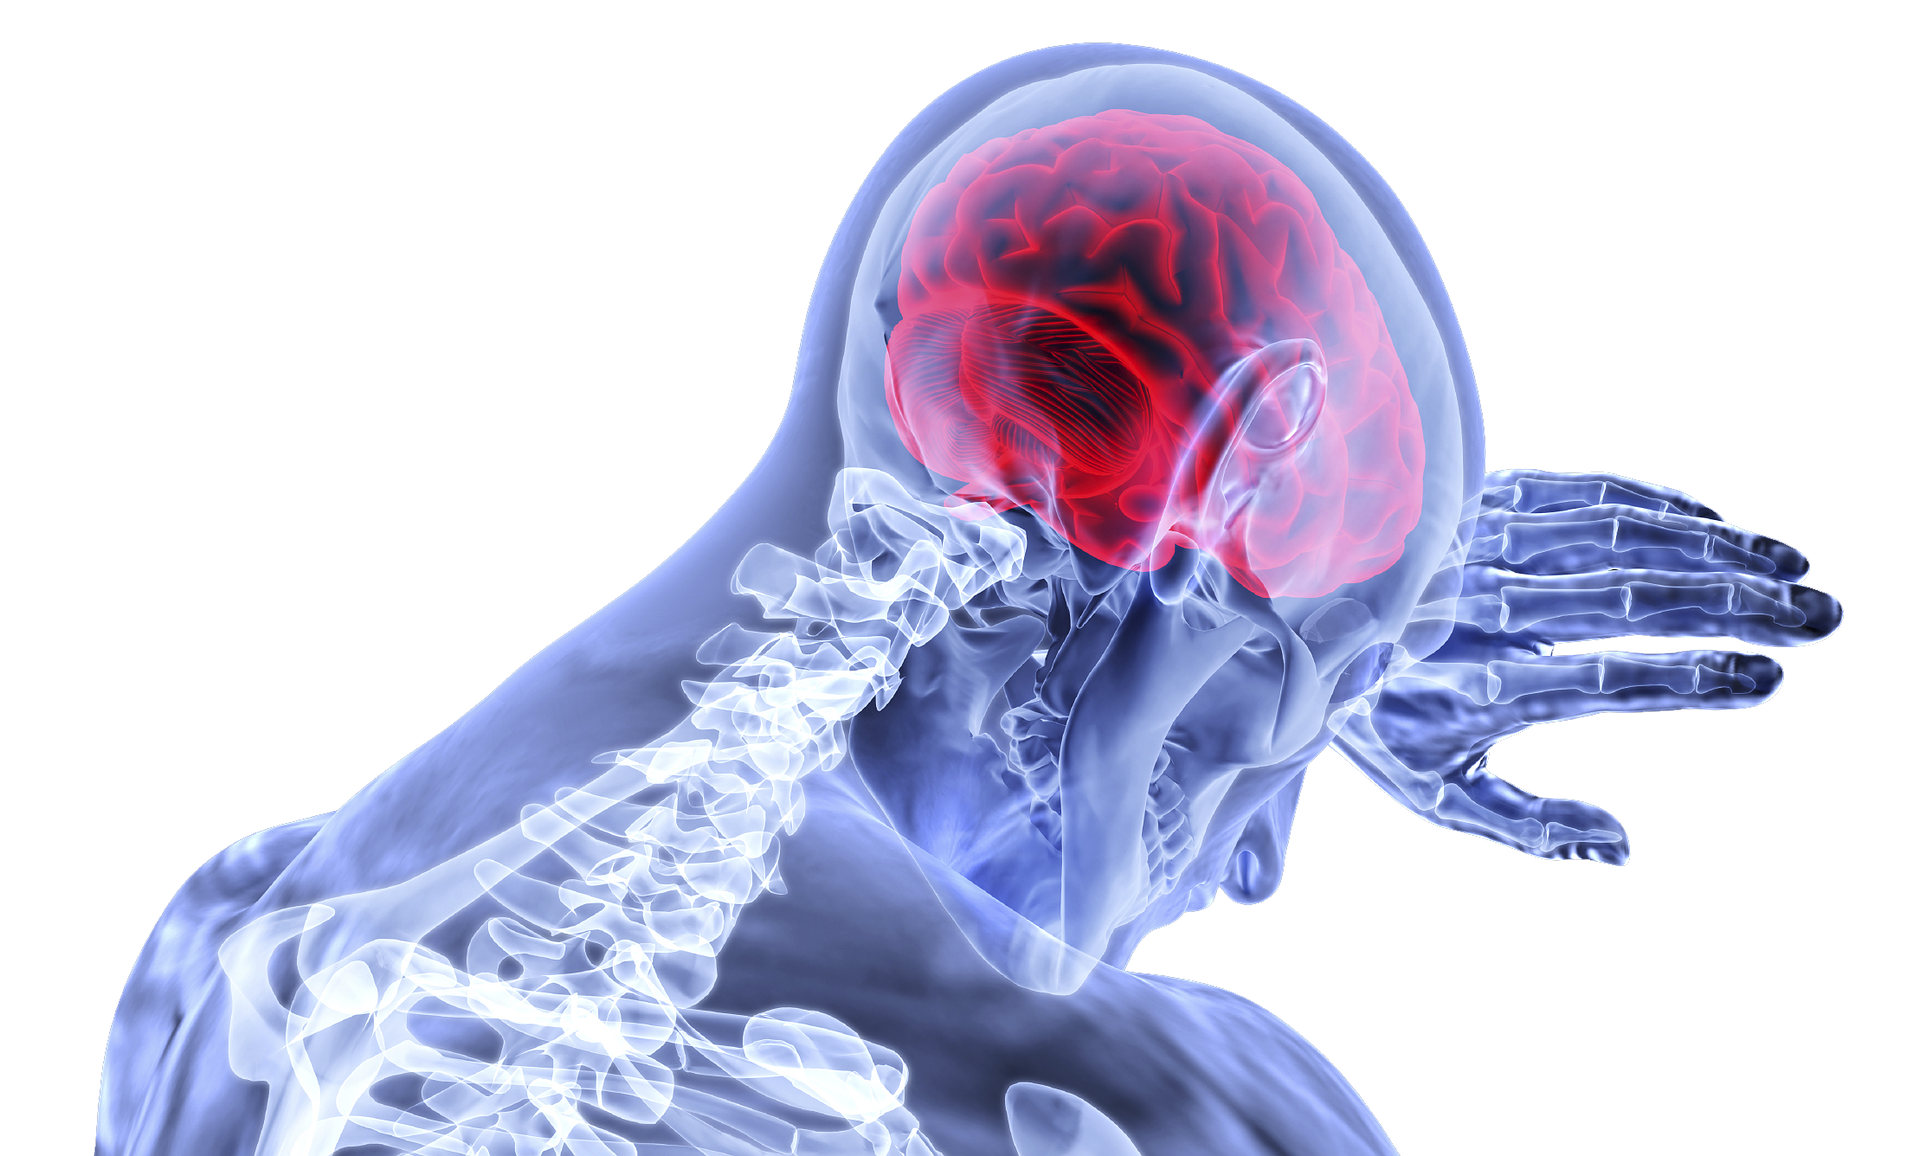

Βίντεο: Οι 15 παράγοντες που αυξάνουν τον κίνδυνο εγκεφαλικού επεισοδίου

Γνωρίζατε πως κάθε περίπου 40 δευτερόλεπτα ένας άνθρωπος στις ΗΠΑ, παθαίνει εγκεφαλικό επεισόδιο;

Υπάρχουν δύο τύποι εγκεφαλικού:

– Το ισχαιμικό, κατά το οποίο διακόπτεται αιφνίδια η παροχή αίματος στον εγκέφαλο και στην πλειοψηφία των περιπτώσεων οφείλεται σε θρόμβο. Περίπου το 80% των εγκεφαλικών επεισοδίων είναι ισχαιμικά.

– Το αιμορραγικό, το οποίο οφείλεται σε διάρρηξη αιμοφόρου αγγείου που προκαλεί διαρροή αίματος και συγκέντρωση στον ιστό που περιβάλλει τον εγκέφαλο, ασκώντας του πίεση.

Δείτε αναλυτικά στο παραπάνω βίντεο τους παράγοντες που αυξάνουν τον κίνδυνο εγκεφαλικού επεισοδίου.